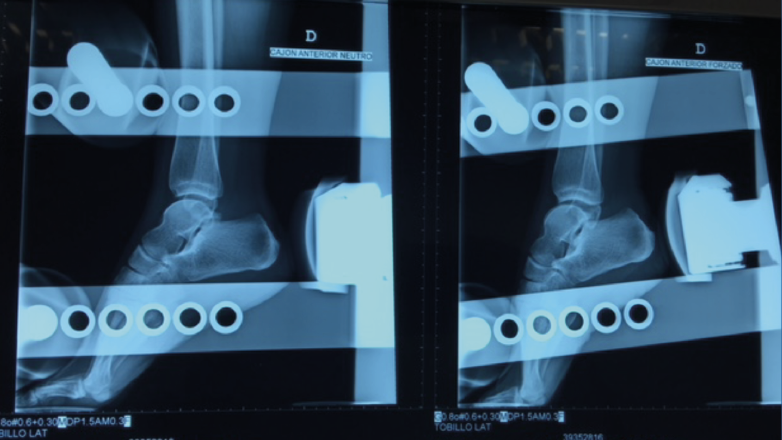

• Valoración de la laxitud articular mediante maniobras ligamentosas(13):

– Cajón anterior: paciente sentado con la rodilla en flexión. Aplicando rotación interna se testa el ligamento peroneo-astragalino anterior (PAA); con rotación externa valoramos la laxitud medial (frecuentemente asociada a dolor anteromedial)(Figura 2).

– Varo forzado: tanto para testar la articulación tibioastragalina como la subtalar. Puede realizarse en decúbito supino o prono.

Figura 2. Maniobra del cajón anterior. Paciente sentado con la pierna colgando a 90°. El cajón anterior con tope óseo pone de manifiesto la insuficiencia del ligamento peroneo-astragalino anterior.